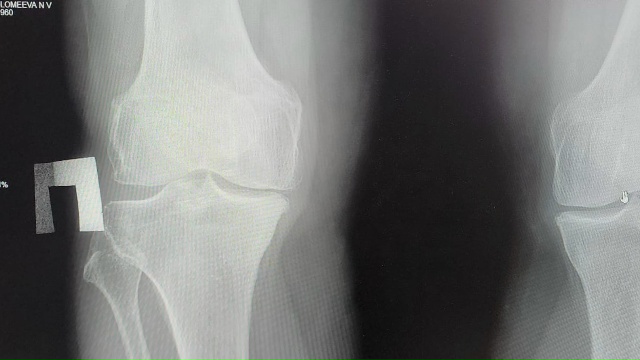

За первую новогоднюю неделю в травмцентре БСМП Рязани оказали помощь 139 гражданам с переломами

Рязанцам напоминили, что травмцентр БСМП оказывает травматологическую, специализированную и неотложную помощи населению с травмами опорно-двигательного аппарата в режиме 7/24 — семь дней в неделю по 24 часа в сутки без выходных и праздников.